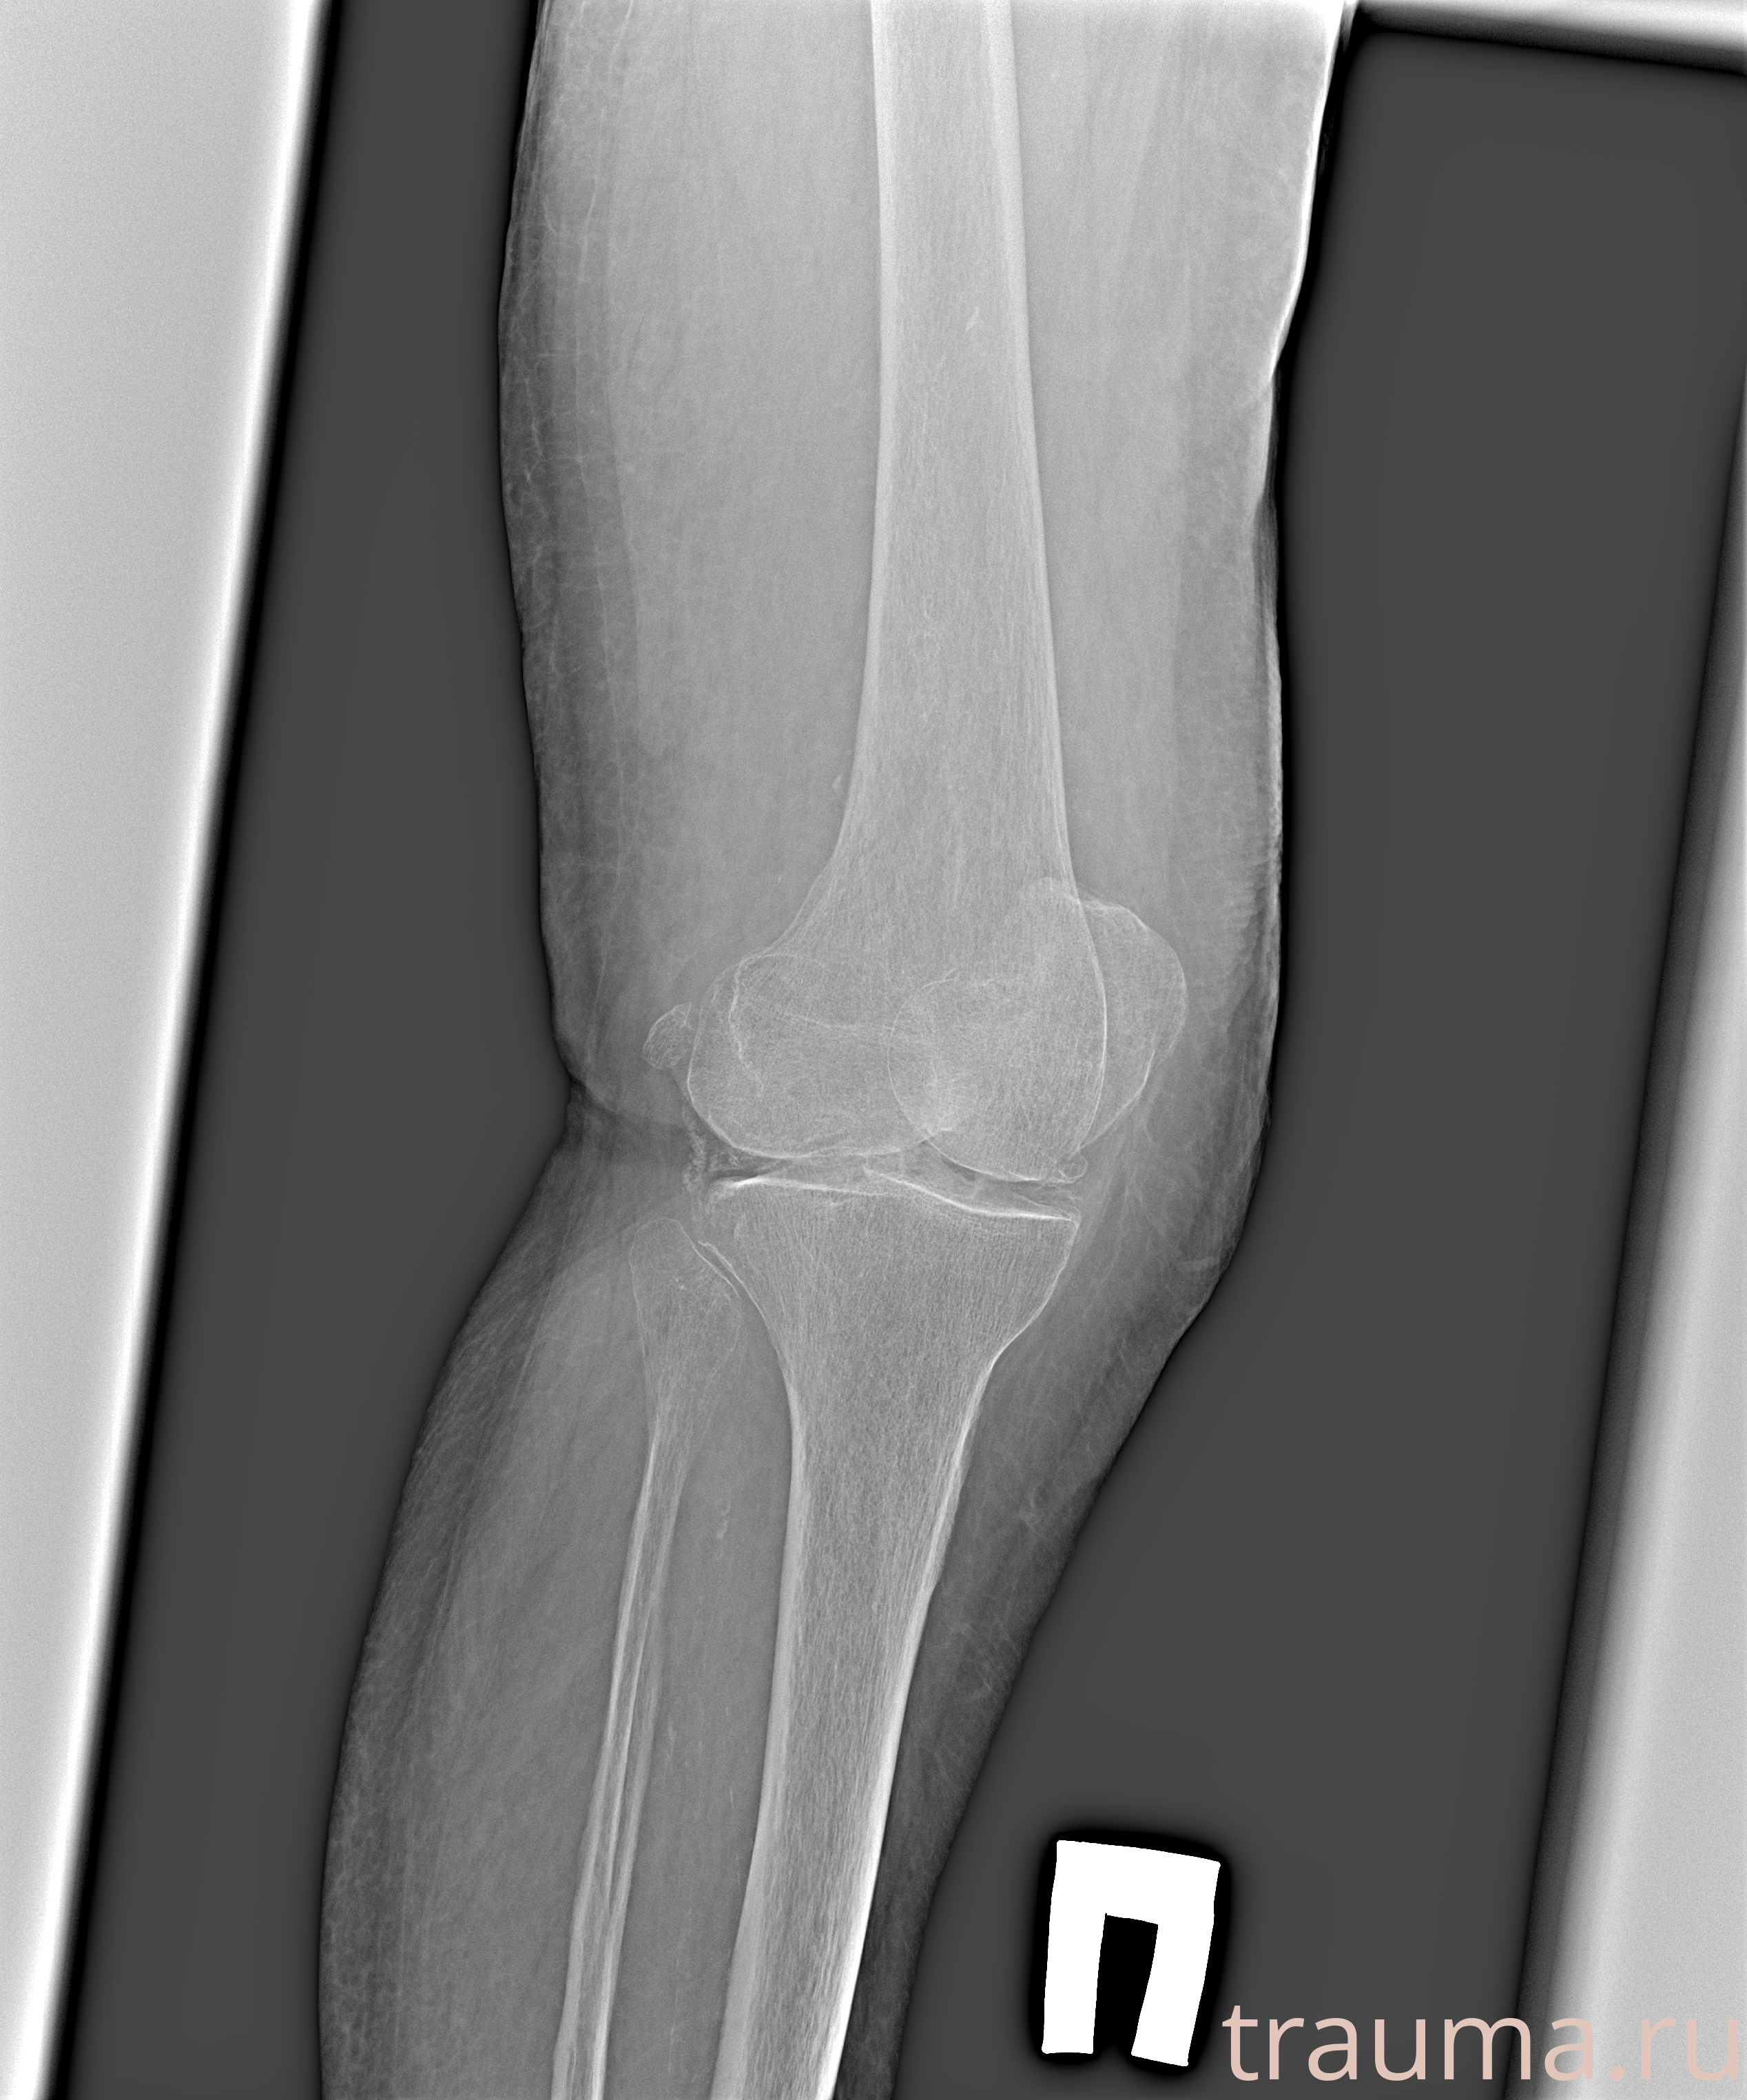

Рентгенограммы